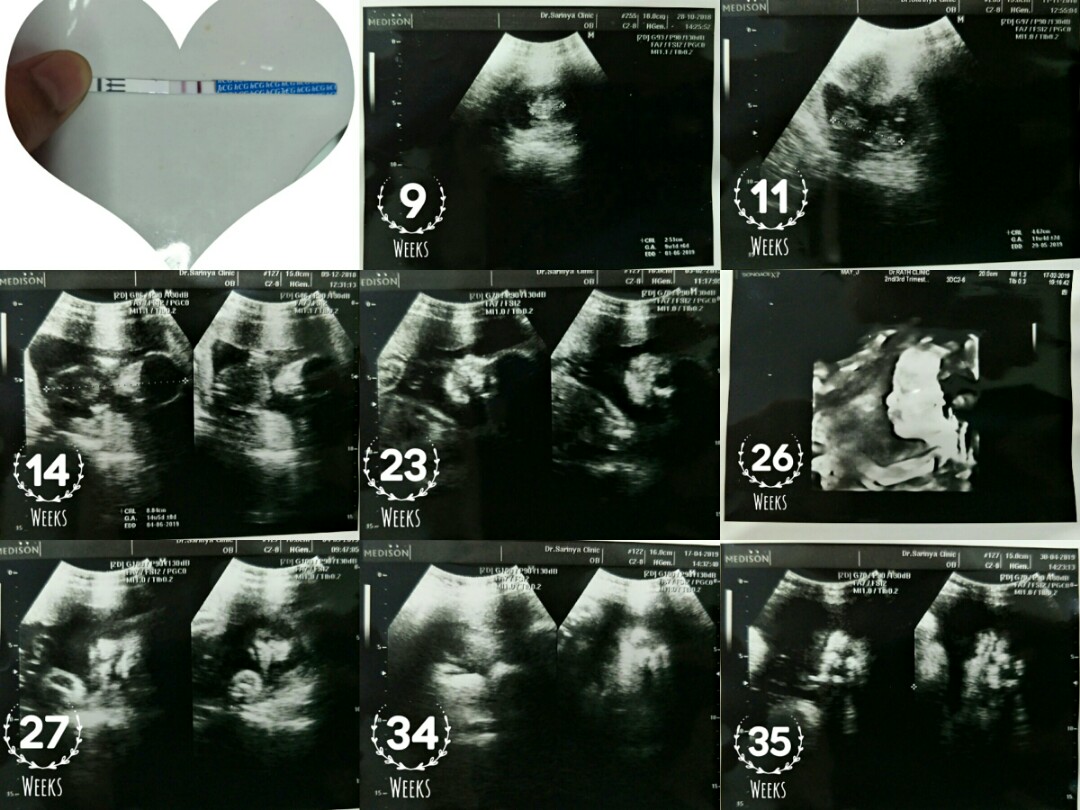

พอดีวันที่ 13 นี้หมอนัดค่ะ อายุครรภ์วันที่นัดก็ประมาณ 13+4 วีค อยากเห็นภาพอัลตร้าซาวด์ของแม่ๆที่อายุครรภ์เท่ากันหรือใกล้เคียงกันค่ะ ว่าน้องมีพัฒนาการถึงไหนแล้ว ?

12วีคค้าาา🥰

ของเราค่ะ